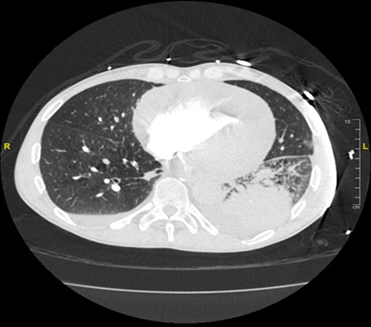

computerized tomography angiography of the chest was performed, revealing a

possible left lower lobe pulmonary embolism. A large pericardial effusion was

also found, with evidence of cardiac tamponade. He was emergently taken to the

cardiac catheterization lab, where a pericardiocentesis was performed and 850

ml of hemorrhagic fluid was evacuated. Cytology of fluid from the left pleural